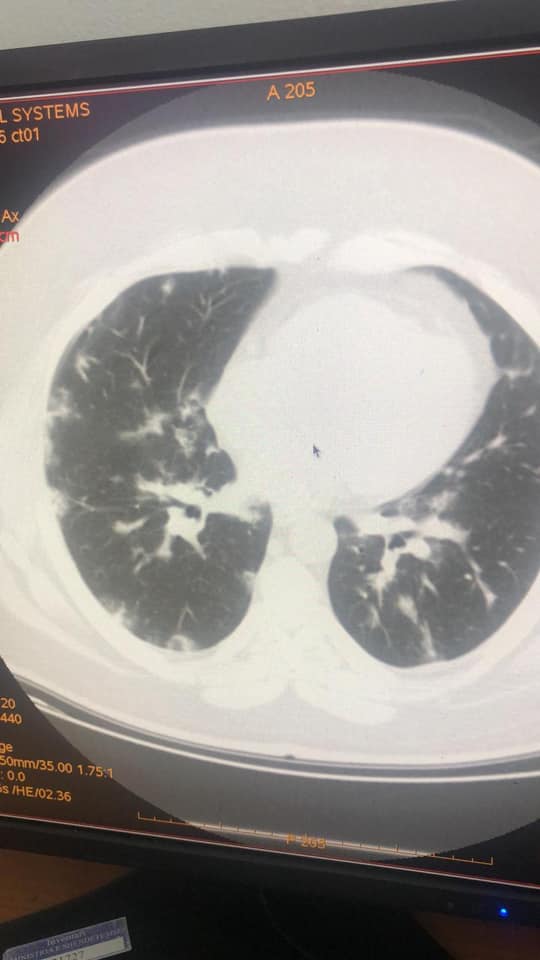

Mjeku Gëzim Xhepa publikon imazhet: Koronavirusi ka qenë në Shqipëri që prej 15 janarit

Koronavirusi ka qenë prezent në Shqipëri që prej datës 15-20 janar. Kështu pretendon mjeku Gëzim Xhepa referuar disa imazheve pulmore të pacientëve që kanë qenë të shtruar në Infektiv në këto data.

Imazhet e publikuara nga mjeku i njohur Gëzim Xhepa, janë evidentuar nga kolegu i tij imazherist Renato Osmani.

Xhepa ka publikuar fotot që tregojnë praninë e koronavirusit që në mesin e muajit janar.

IMAZHET E JANARIT QË FLASIN PËR PREZENCËN E COVID-19 NË SHQIPËRI QË NË KËTË PERIUDHË

Sot, falë mikut dhe kolegut tim të nderuar Dr. Renato Osmani…, imazhëristit që ishte i pari, që javën e parë pas zbulimit të të ashtuquajturit rast 0, identifikoi fizionominë dhe identitetin imazhërik pulmonar të COVID-19… dhe potencën e ekzaminimit CT ndër ekzaminimet e skemës bazë për diagnostikim dhe përcaktim prognose…, mu ofruan imazhe të pakundërshtueshme të prezencës së COVID-19 në datat 15 – 20 janar, në disa raste në Infektiv…!!!

Faleminderit Dr. Renato…, jo vetëm për menaxhimin pa panik, por me vigjilencë të situatës së karantinës, nëpërmjet centarlizimit dhe koordinimit nacional imazhërik për suspektim sa më të hershëm të sëmundjes dhe prevenimin e kaosit, që mund të kish shkaktuar strategjia e gabuar e numrit 127…, por edhe për ndihmën që po jep për Komitetin Teknik për konfuzionin në pritjen e pikut epidemiologjik…!!! Po ju ofroj pamjet imazhërike të pesë rasteve, duke ju kujtuar që janë pronë intelektuale e Dr. Renato Osmani dhe i publikoj me aprovimin e tij, duke mbrojtur të drejtën e tij të aitorit…!!!